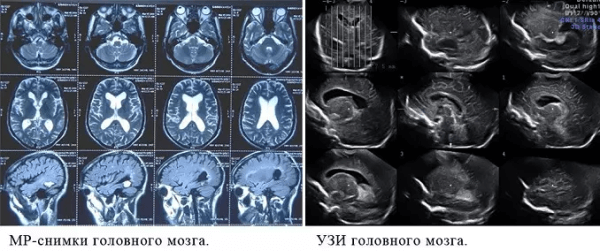

Что показывает МРТ

Магнитно-резонансная томография или МРТ - это сфокусированный метод, который проводит очень детальное обследование. Диагностическая точность МРТ превышает УЗИ и во многих случаях КТ, за исключением сканирования полых органов (легких, желудка, кишечника) и костей. МРТ является золотым стандартом диагностики:

- заболеваний головного и спинного мозга;

- патологий суставов;

- межпозвоночных дисков;

- сердца и сосудов;

- болезней гинекологического, проктологического и урологического характера.

В отличие от быстрого КТ и УЗИ, магнитно-резонансное обследование требует времени - в среднем пациенту нужно лежать в томографе и соблюдать неподвижность 30-60 минут.

Принцип работы МРТ основан на эффекте ядерного магнитного резонанса. МР томограф в своей конструкции имеет мощный магнит, который создает магнитное поле, и датчик, который подает радиочастотные сигналы. В такой ситуации протоны атомов водорода начинают колебательные движения, выделяя при этом импульсы. Их улавливает компьютер томографа и преобразовывает в трехмерные изображения. Чем больше воды содержится в клетках ткани, тем детальней получается ее изображение. Поэтому на МРТ хорошо отображаются органы с большим содержанием воды: МРТ головного мозга, МРТ спинного мозга, МРТ глазных орбит, МРТ органов малого таза, МРТ позвоночника, МРТ суставов, и плохо визуализируются органы с большим содержанием воздуха МРТ органов грудной клетки или кости.

Основы преимуществом МРТ перед КТ и рентгеном является отсутствие в ходе сканирования какого-либо излучения. А вот недостатком этого метода диагностики будет ряд ограничений - наличие ферромагнитного металла в теле пациента и имплантированных в организм водителей ритма, несовместимых с МРТ.

Что покажет УЗИ

Ультразвуковое исследование или УЗИ - это широко распространенный вид обследования, активно применяемый в диагностических центрах СПб. В ходе данной процедуры диагностика проводится с помощью ультразвуковых волн. Проходя через границы тканей различной плотности, ультразвук по-разному отражается от них. Ультразвуковая установка имеет датчик, который посылает ультразвуковой сигнал, а затем фиксирует ответ и переводит его в графическое изображение. Таким способом врачи могут хорошо обследовать:

- органы малого таза;

- органы брюшной полости;

- лимфоузлы и молочные железы;

- мягкие ткани;

- сосудистую систему.

К сожалению, серьезным препятствием для ультразвука являются кости, через которые сигнал пробиться не может. Поэтому малоинформативным является

- УЗИ головного мозга

- УЗИ сердца

- УЗИ органов средостения

- УЗИ позвоночника.

Основным достоинством УЗИ является отсутствие каких-либо противопоказаний и ценовая доступность. По диагностической ценности и точности УЗИ безусловно уступает МРТ и КТ, однако является приоритетным профилактическим и скрининговым методом обследования для многих заболеваний, включая патологии мочеполовой системы у мужчин и женщин, рака молочных желез и органов брюшной полости, воспалений мягких тканей.